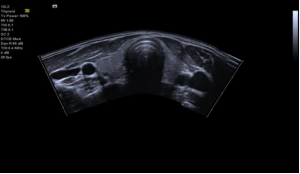

➢ 小儿解决方案

高效:

小儿颅脑、小儿心脏、小儿腹部一次性获得检查结果

优异:

基于良好的成像平台及探头技术,获得优异的图像质量